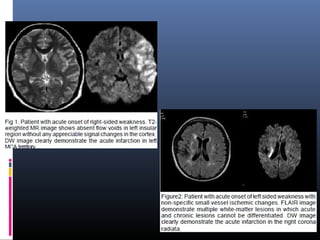

 Most pathologic processes show increased SI on T2-WI, and the conspicuity of

lesions that are located close to interfaces b/w brain parenchyma and CSF may be

poor in conventional SE or FSE T2-WI sequences.

 FLAIR images are heavily T2-weighted with CSF signal suppression, highlights

hyperintense lesions and improves their conspicuity and detection, especially when

located adjacent to CSF containing spaces

 Focal cortical dysplasia of Taylor’s balloon cell type- markedly hyperintense

funnel-shaped subcortical zone tapering toward the lateral ventricle is the

characteristic FLAIR imaging finding

 Embolic infarcts- Improved visualization

 Chronic infarctions- typically dark with a rim of high signal. Bright peripheral zone

corresponds to gliosis, which is well seen on FLAIR and may be used to

distinguish old lacunar infarcts from dilated perivascular spaces.